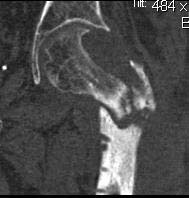

If there is no osteomyelitis, I would recommend open insertion of Gamma Nail

and Bone Grafting.

кт